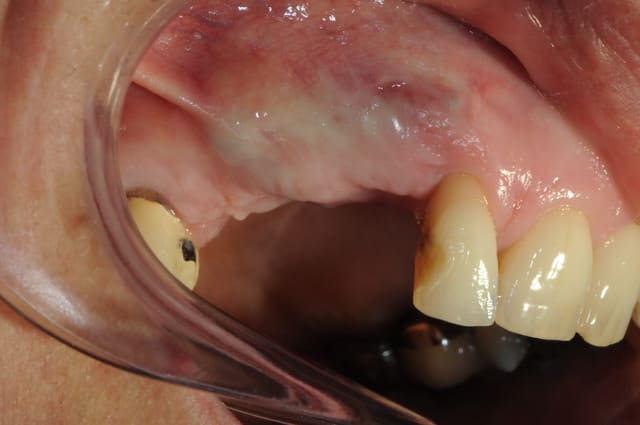

pour pluton, je viens de poser les implants le cas n'est pas fini

très joli dudule...j'aurai fait pareil...et pas de conjonctif palatin non plus dans ce cas en prime intention...mieux vaut se le réserver pour la phase implantaire (à la pose ou au désenfouissement si technique 2 temps

bien aussi béo...des photos du cas fini?